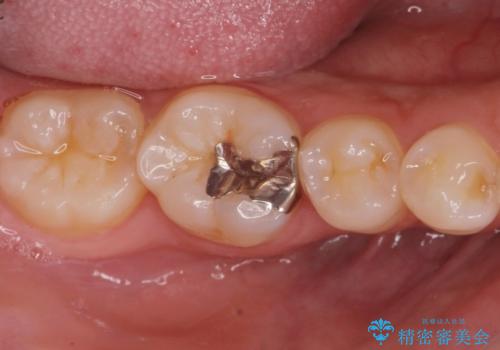

口を開けたら銀が目立つのが気になる。

- 銀が目立つので白くしたいとの事で来院。

銀の詰め物を拡大鏡下で取り除き、う蝕がないことを確認してから

ZrCrの被せ物で治療を行いました。